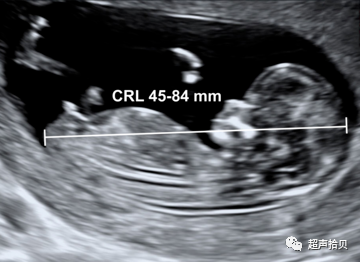

测量NT的最佳孕周是:11+0~13+6周。测量时,头臀径(CRL)应在45mm~84mm之间。

• 选择孕11周做为NT最早的检查时间,理由如下:

(1)筛查需有诊断性检查跟进,但11周前进行的绒毛活检术与胎儿横向截肢畸形有关;

(2)如果NT检查的最小孕周为11周,很多严重的胎儿畸形就可以在NT扫描的同时被诊断出来

• 选择13周+6天做为检查时间的上限,理由如下:

(1)受累胎儿的母亲可在早孕期而非中孕期选择终止妊娠;

(2)染色体异常胎儿颈项透明层异常增厚的发生率在13周后降低;

(3)13周以后,胎儿呈直立位,难以获得理想的检查平面,使准确测量NT的成功率降低。